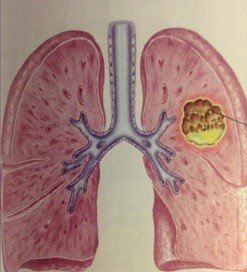

Şəkil 10. Ağciyər absesinin yaranma mexanizmləri və gedişi

Klinik təsnifatda ağciyər xərçəngi 3 mərhələyə bölünür:

- Erkən mərhələ - mediastinal yayılma yoxdur (I-II mərhələlər)

- Yerli yayılmış mərhələ - mediastinuma yayılma var (IIIA və B mərhələlər)

- Metastaz mərhələsi - distal metastazlar var (IV mərhələ) (Şəkil 10).